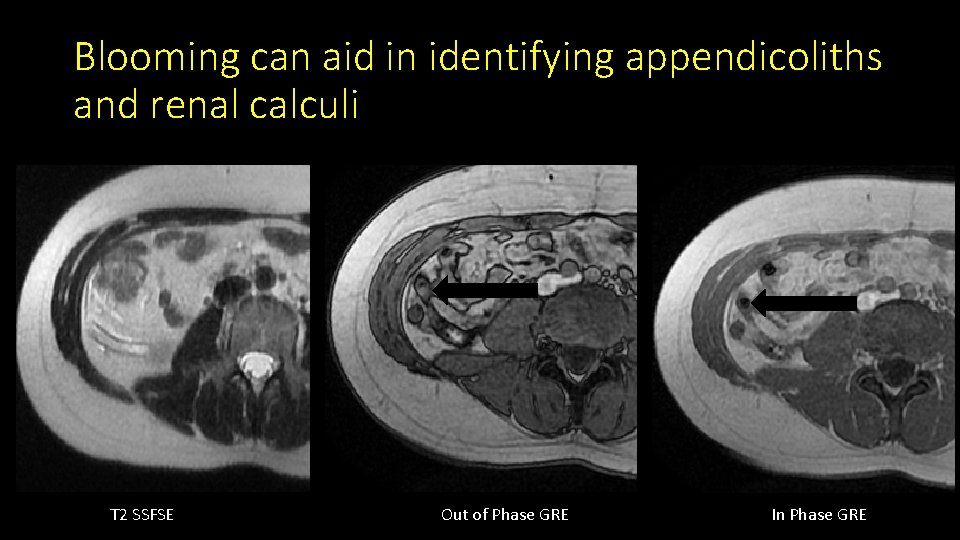

Blooming can aid in identifying appendicoliths and renal calculi T 2 SSFSE Out of Phase GRE In Phase GRE